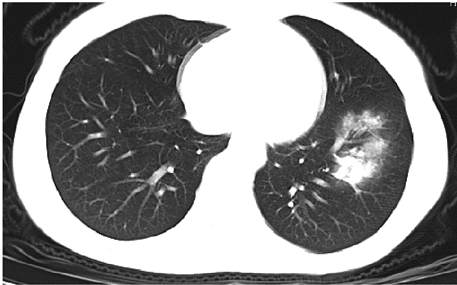

A wide variety of typical and atypical CT abnormalities have been reported for COVID-19 patients in various studies [58, 59]. So, we tested our models on external CT images extracted from these two publications as they feature typical findings of COVID-19 pneumonia marked by specialists. In order to make sure that not any of the extracted images are unintentionally included in our datasets, specifically the COVID19-CT dataset, we use the model trained on the SARS-CoV-2 dataset. First, the InceptionV3 model is employed to classify the extracted CT images. The model is able to correctly classify the given CT images as COVID-19. Second, in order to interpret the model’s generalization capabilities, we apply the Grad-CAM technique to visualize the regions of abnormalities that are considered. By assessing the different CT images in Figure 15, we can see that the model accurately localizes the disease-related regions. Even more interesting is the fact that the model ignores any specific marks in the images like letters and only localizes the COVID-19 related regions. These visual explanations show the success of our models to learn relevant, generic visual features related to COVID-19 and are capable to correctly classify CT images outside the datasets on which they are trained.

Figure 16 shows various CT scans where only one lung is visible. The CT scans are also extracted from the paper [58] and show different CT manifestations of COVID-19 pneumonia marked by red squares. The InceptionV3 model is capable to classify them correctly as COVID-19, although it is trained on CT scans where the entire lung is visible. Intriguingly, when applying Grad-CAM we can see that all regions of abnormalities are accurately localized. This also proves the potential of our model to detect COVID-19 abnormalities in CT images outside the dataset used for training.